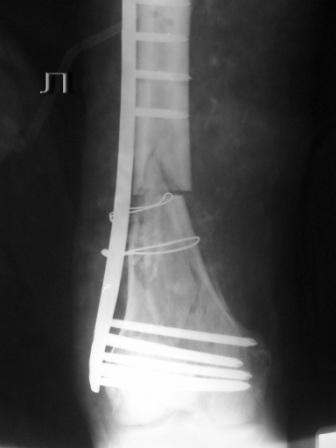

Пациенту 50 лет. 24.11.09 сделали л\бедро.